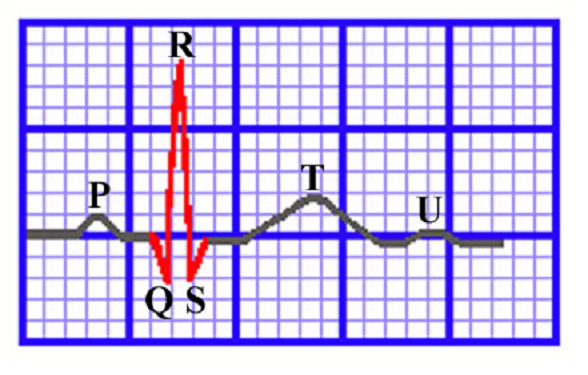

一、正常的QRS波群

QRS波群(QRS interval):表示心室的除极化

1、在时间上

QRS波群正常的时间为0.06~0.10s,如图1红色曲线所示,也就是1.5到2.5小格,绝对不会超过3个小格(课本上说是0.11s,但我都是按照3个小格记得,因为半格的差别如果不是用分规测量,很难发现,而且如果QRS波起点定的不一致也会导致0.5小格的差别,因此还不如记3小格,当然对于心电专业的还是不要忽略这0.5小格)。QRS波群的第一个变态行为就是和时间有关的,所以这3小格必须记住。

图1

2、在高低上

本来想写振幅的,想想还是高低显得实在通俗,正常的QRS波群主要显示的R波和S波,在此我着重强调胸导联,如图2所示,从V1到V6到,R波是逐渐变高,S波是逐渐变低,我用了红蓝两条线表示出了R波和S波的大体趋势。

我们来看看书上是咋说的:正常人V1、V2导联多呈rS型,V1导联的R波≤1.0mV。V5、V6导联可呈qR、qRs、Rs或R型,V5、V6导联的R波≤2.5mV。在V3、V4导联,R波和S波的振幅大体相似,V1~V6导联R波逐渐增高,S波逐渐变小,V1的R/S<1,V5的R/S>1。

是不是晕了,其实记住下面的图,其他的不用管它了。至于肢体导联,我总结了一点:QRS波群的主波方向应与P波的方向一致。也就是说肢体导联上P波向下,那么同导联的QRS波群主波方向也应该与之相同,否则就是异常,至于是否有意义,就得结合临床了。

最后再说一点关于高低的问题,那就是QRS波群低电压,其实就是身高先天不足呗,而且即使把R波和S波的身高加起来还是不够高,肢体导联是不够1大格(5小格),也就是刚刚≤0.5mv,胸导联是不够1.6大格(8小格),也就是≤0.8mv。

图2